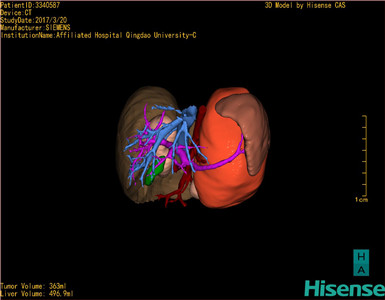

术前三维重建及手术方案设计:

将0.625mm双源薄层CT资料的静脉期和动脉期Dicom格式文件导入海信CAS系统。

通过调节窗宽窗位调整CT序号,对肿瘤,肝实质,胆囊,下腔静脉,肿瘤,肝动脉、门静脉及肝静脉等进行三维重建;系统自动计算肿瘤体积和肝脏体积。

模拟手术操作,自动计算切除肿瘤体积。肝脏体积为496.9ml,肾上腺肿瘤体积363ml,术前规划手术方案,进行手术。

术前三维重建:

重建图片